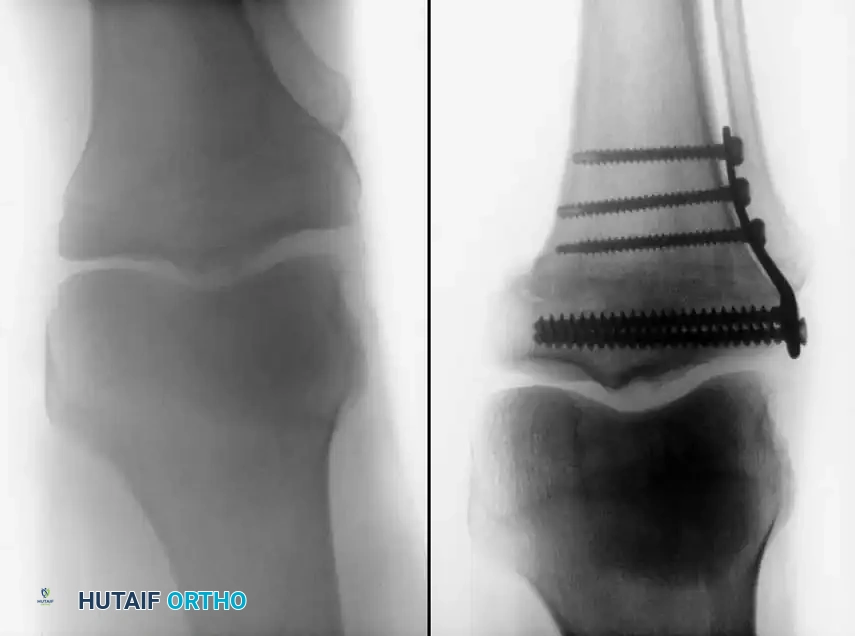

1. Lateral Closing Wedge HTO: Involves removing a laterally based wedge of bone from the proximal tibia and fixing the osteotomy with a plate or staples. It requires a fibular osteotomy or proximal tibiofibular joint disruption.

2. Medial Opening Wedge HTO: Increasingly popular due to the avoidance of the peroneal nerve and preservation of bone stock. A medial osteotomy is created, opened to the desired correction angle, and stabilized with a rigid locking plate. The void may be filled with allograft or synthetic bone substitute.

Surgical Atlas: Osteotomy and Realignment Biomechanics

The following radiographic and illustrative figures detail the preoperative planning, biomechanical axes, and intraoperative fixation strategies critical for successful osteotomies around the knee.

Intraoperative fluoroscopy is utilized to confirm the osteotomy trajectory. Guide pins are placed parallel to the joint line, ensuring the hinge point remains intact to provide intrinsic stability to the osteotomy site.

Rigid internal fixation is achieved using anatomically contoured locking plates. In opening wedge osteotomies, the plate acts as a buttress to maintain the correction angle while the osteotomy heals.

Careful soft tissue management is required. In medial opening wedge HTO, the superficial medial collateral ligament (sMCL) must be partially released distally to allow the osteotomy to open without increasing medial compartment contact pressures.

For distal femoral osteotomies, the plate is typically applied to the medial or lateral cortex depending on the wedge orientation. The fixation must be robust enough to withstand the significant bending moments present at the distal femur.